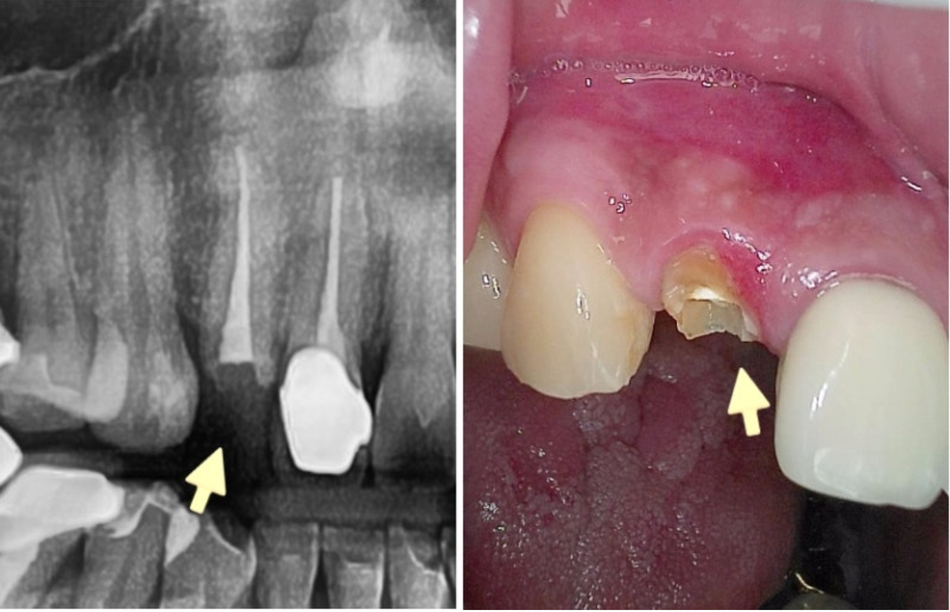

Hãy cùng xem trường hợp bệnh nhân dưới đây.

Những lỗ sâu đen có thể nhìn thấy rõ ràng

bên trong chiếc răng nơi mão răng bị rơi ra.

▲ Sâu răng bên trong thân răng

Bệnh nhân dưới đã sử mão răng vàng trong 15 năm.

Mão răng rơi ra và bạn đến gặp nha sĩ với mão răng vẫn còn dính trên răng.

Nếu nhìn vào bức ảnh, bạn có thể thấy mão răng có những vết nứt ở đây và ở đó.

▲ Vết nứt và mòn trên mão răng cũ

Có thể thấy nướu xung quanh chân răng đã chảy máu

và xương hàm đang dần tiêu tan.

Thông thường, trong những trường hợp như thế này, khả năng cao là bên trong

đã mục nát rất nhiều do vi khuẩn gây sâu răng sinh sôi qua các vết nứt.

Khi tôi tháo mão răng ra, như đã dự đoán bên trong đã mục nát rất nhiều.

▲ Răng mục nát bên trong mão răng cũ